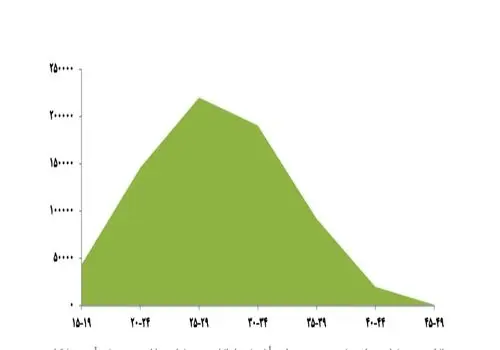

وی ادامه داد: مطالعات انجام شده در معتبرترین دانشگاههای جهان نشان میدهد که با هر بارداری، میزان سرطان سینه (شایعترین سرطان در زنان) کاهش مییابد. این اثر محافظتی تا ده سال پس از بارداری ادامه دارد. همچنین خطر سرطان رحم با هر بارداری حدود ۲۰ تا ۲۵ درصد کاهش مییابد. زنانی که تاکنون باردار نشدهاند (نولیپار)، نسبت به مادران در معرض ریسک بالاتری از سرطان قرار دارند.